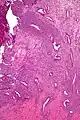

| Micrograph of a uterine adenosarcoma showing a mitotically active malignant stroma and benign glands. H&E stain. | |

Uterine adenosarcoma is an uncommon form of cancer that arises from mesenchymal tissue of the uterus and has a benign glandular component.

Uterine adenosarcoma have, by definition, a malignant stroma and benign glandular elements. The World Health Organization (WHO) criteria have a mitotic rate cut point; however, this is often disregarded, as bland-appearing tumours with a low mitotic rate are known to metastasize occasionally.[2]